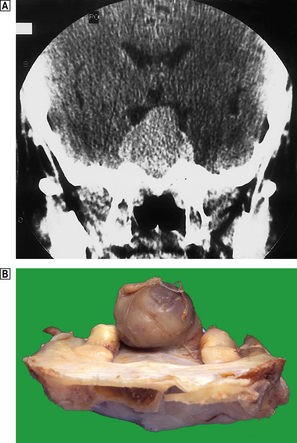

These may be either on the surrounding pituitary to produce hypofunction, or on the overlying optic chiasma (Fig. 17.7), producing a characteristic visual field defect called bitemporal hemianopia. Further growth may compress the hypothalamus.

image

Fig. 17.7 Pituitary adenoma.image Coronal plane CT scan of the pituitary fossa showing the sella turcica widened by a pituitary adenoma, which is compressing the optic chiasma and hypothalamus.image Pituitary adenoma revealed at autopsy, protruding above the sella turcica.